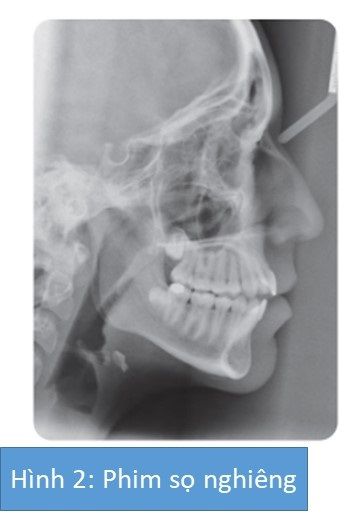

Bệnh nhân nữ 15 tuổi có sai lệch khớp cắn hạng I trên nền xương hạng II nhẹ với kích thước dọc tăng, phức tạp bởi chen chúc nhẹ, cắn chéo răng sau một bên cùng với lệch lạc và cắn hở phía trước.